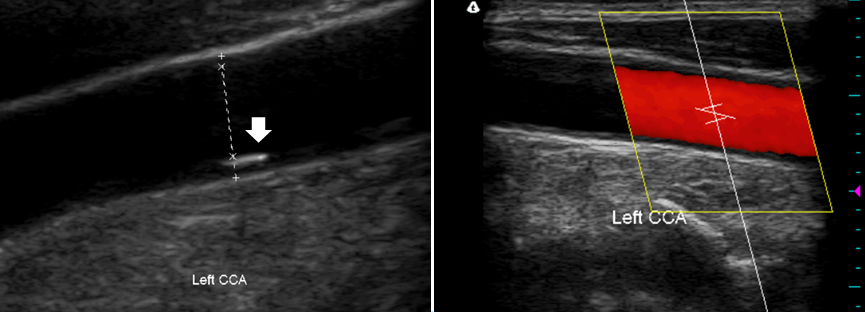

경동맥

협착을 진단하는 방법은 여러가지가 있다. 비교적 간단하게 할 수 있는 검사로 경동맥 초음파 검사가

있다. 경동맥 초음파 검사는 초음파를 이용하여 경동맥 혈관벽의 두께와 죽상경화반 유무 및 경동맥

협착 정도를 확인하는 검사이다. 외래에서 검사할 수 있고 별도의 준비가 필요하지 않아 고혈압, 당뇨병 등의 위험인자가 있는 환자에서 경동맥 협착 여부를 확인하는 선별 검사로 자주 이용된다.